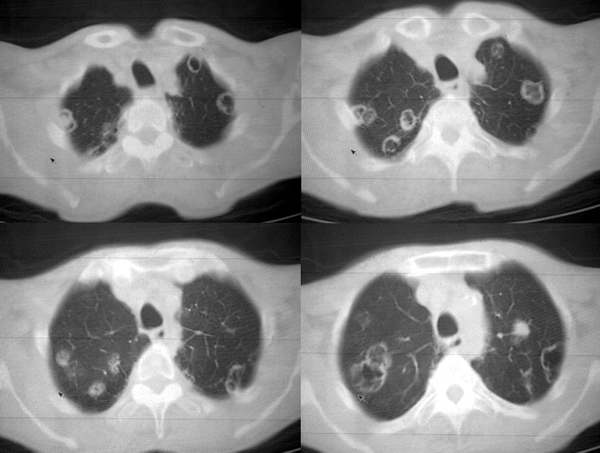

男62肺癌治疗后复查

具体治疗措施不清楚,治疗前空洞很少,请讨论空洞的性质

双肺内及胸壁旁见有多发软组织实性阴影和空洞,实性病变多见有脐凹切迹,贴近胸膜的见有胸膜凹陷征;空洞的壁多为厚薄不均,形态不规则,纵隔内见有较多肿大淋巴结,诊断为双肺内转移性病变。

双肺内及胸壁旁见有多发软组织实性阴影和空洞,实性病变多见有脐凹切迹,贴近胸膜的见有胸膜凹陷征;空洞的壁多为厚薄不均,形态不规则,纵隔内见有较多肿大淋巴结,诊断为双肺内转移性病变。[气囊或孔洞实为腺癌缘肺泡壁生长所致]

右肺门软组织块影,右主支气管及中间段支气管管壁明显增厚,两肺内多发结节及大小不等的类圆形薄壁空洞,纵隔内多发肿大的淋巴结;

考虑:1.右中央型肺癌伴两肺广泛性转移及纵隔转移。

2.多发性空洞需和霉菌性空洞鉴别。